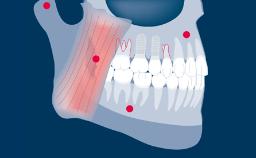

A substituição de dentes perdidos por meio de implantes endósseos tem provado ser uma modalidade de tratamento bem-sucedida para pacientes total e parcialmente desdentados. Este conceito é baseado no fenômeno biológico da osseointegração. Para um bom resultado a longo prazo de uma reconstrução implantossuportada, os tecidos duros e moles precisam ser estáveis e fornecer um suporte adequado para a reconstrução protética. Existem vários fatores de risco que podem afetar as taxas de sucesso e sobrevivência. Um clínico que planeja uma terapia com implantes precisa conhecer os fatores de risco que contribuem para os diferentes tipos de complicações que podem ocorrer após o tratamento.

- identificar os diferentes tipos de complicações que podem estar envolvidas na terapia com implante

- identificar os fatores de risco para essas complicações